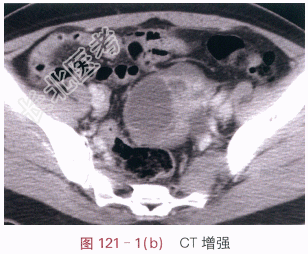

影像学资料如图121-1~图121-3所示。

读片分析:左侧附件区囊实性不规则形肿块,CT增强后实性部分的边缘呈明显强化,中心坏死部分强化不明显,未见肿大淋巴结和腹水征象。多平面重建后可见,左输尿管下段后累及,其中上段积水扩张。